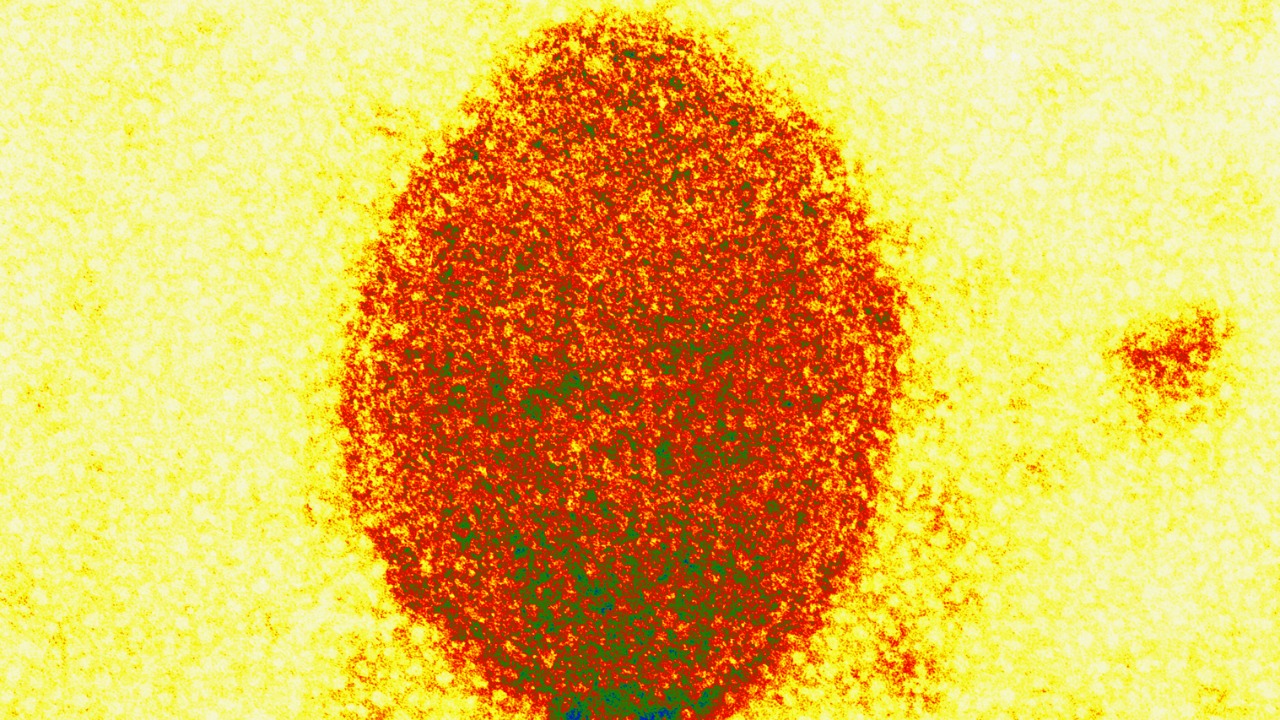

Monkeypox Virus

Monkeypox is a viral disease resembling smallpox, albeit less severe. It is endemic to parts of Africa but has recently appeared in other regions, raising concerns about its potential for widespread transmission. The virus is transmitted to humans through close contact with infected animals or humans.

Symptoms include fever, rash, and swollen lymph nodes. While most cases are mild, severe cases can occur, especially in vulnerable populations. Ongoing monitoring and vaccination campaigns are crucial in limiting outbreaks and preventing further spread.